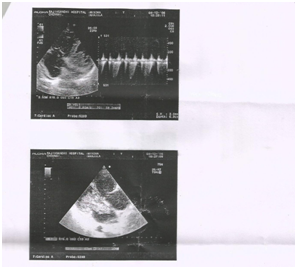

64 year old female who presented with dyspnea for two months duration was evaluated in our department. Echocardiogram showed a cauliflower like mass with multiple protruding villous appearance attached to the inter atrial septum near the foramen ovale suggestive of left atrial myxoma traversing the mitral valve orifice causing mitral valve obstruction. Patient was referral to cardiothoracic surgeon for surgical excision.

We present a 64_ year old female who presented with symptoms of dyspnea NYHA class III, and palpitations for two months duration. Clinical examination revealed pallor, and a mid diastolic murmur in mitral area. ECG was within normal limits. Echocardiogram showed a cauliflower like mass with multiple protruding villous appearance attached to the inter atrial septum near the foramen ovale traversing the mitral valve orifice causing mitral valve obstruction. Patient was referred to cardiothoracic surgeon for surgical excision (Figure 1 & 2).

Figure 1 Clinical examination 1.